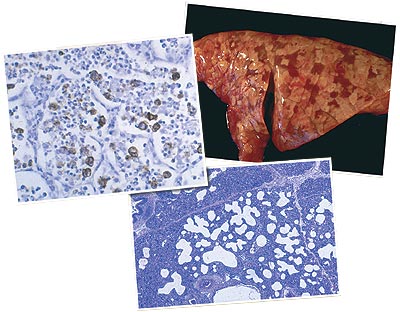

Quelles lésions peuvent être attribuées au PCV2 ?

Pneumonie interstitielle très probable. Conséquence habituelle de l'infection par le PCV2, même si elle peut être provoquée par d’autres virus, dont celui du SDRP ou par l’effet synergique de plusieurs virus.

Atteinte des ganglions lymphatiques

Conséquence caractéristique de l'infection par le PCV2 chez des animaux qui développent cliniquement la MAP. Cela est lié à une profonde atteinte et à une modification des populations de cellules lymphoïdes.

Nécrose des ganglions lymphatiques

C'est une conséquence occasionnelle ou très occasionnelle de l'infection par le PCV2 d'animaux développant la MAP.